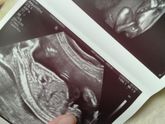

Ну вот показали нам мужское достоинство нашего парня!)) Мы уже большие — нам оказалось на неделю больше, чем определяли на первом УЗИ — 20 недель и 4 дня ✌? Мы здоровы, что самое главное ??